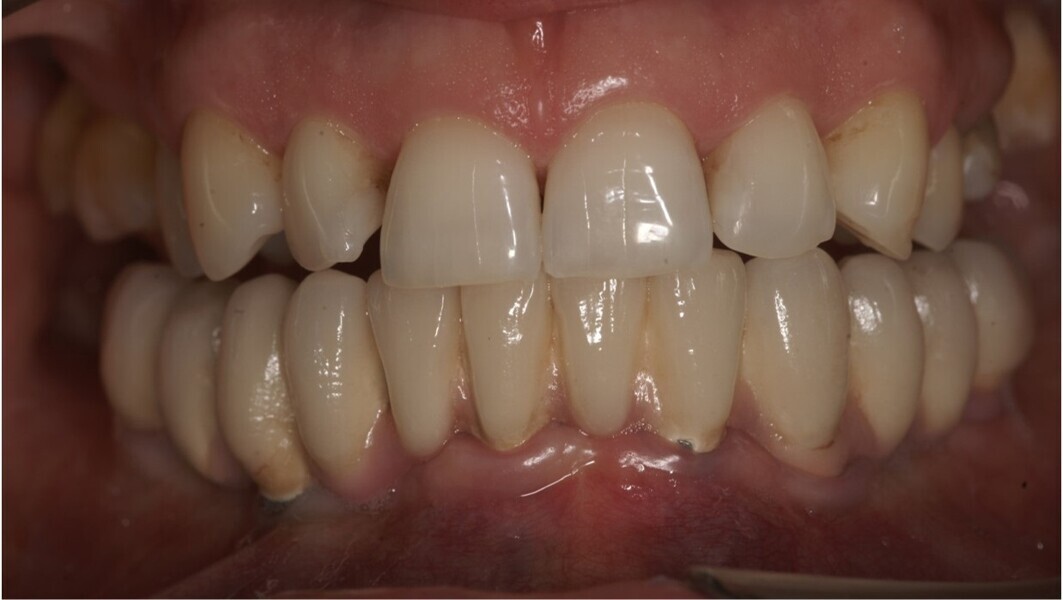

Natychmiastowa implantacja i zaopatrzenie protetyczne pacjentów z zaawansowaną chorobą przyzębia